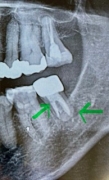

画像2

歯の根の下に黒っぽい場所(黄緑でマーキング親知らず側)があってそこから歯茎の方に膿が出ている。

CT画像からはハッキリ破折を認められない。

少し線が見える場所が6番の歯側にあるが、黄緑でマーキングした場所は根幹治療で薬が入っているところと根の治療の境目で破折ではない可能性もある とのこと。

奥歯7番は根幹治療をしてもなかなか難しい場所で、根の形がCTで見ると、Cという文字のようなかたちでつながっていると、余計難しいとのことでした。